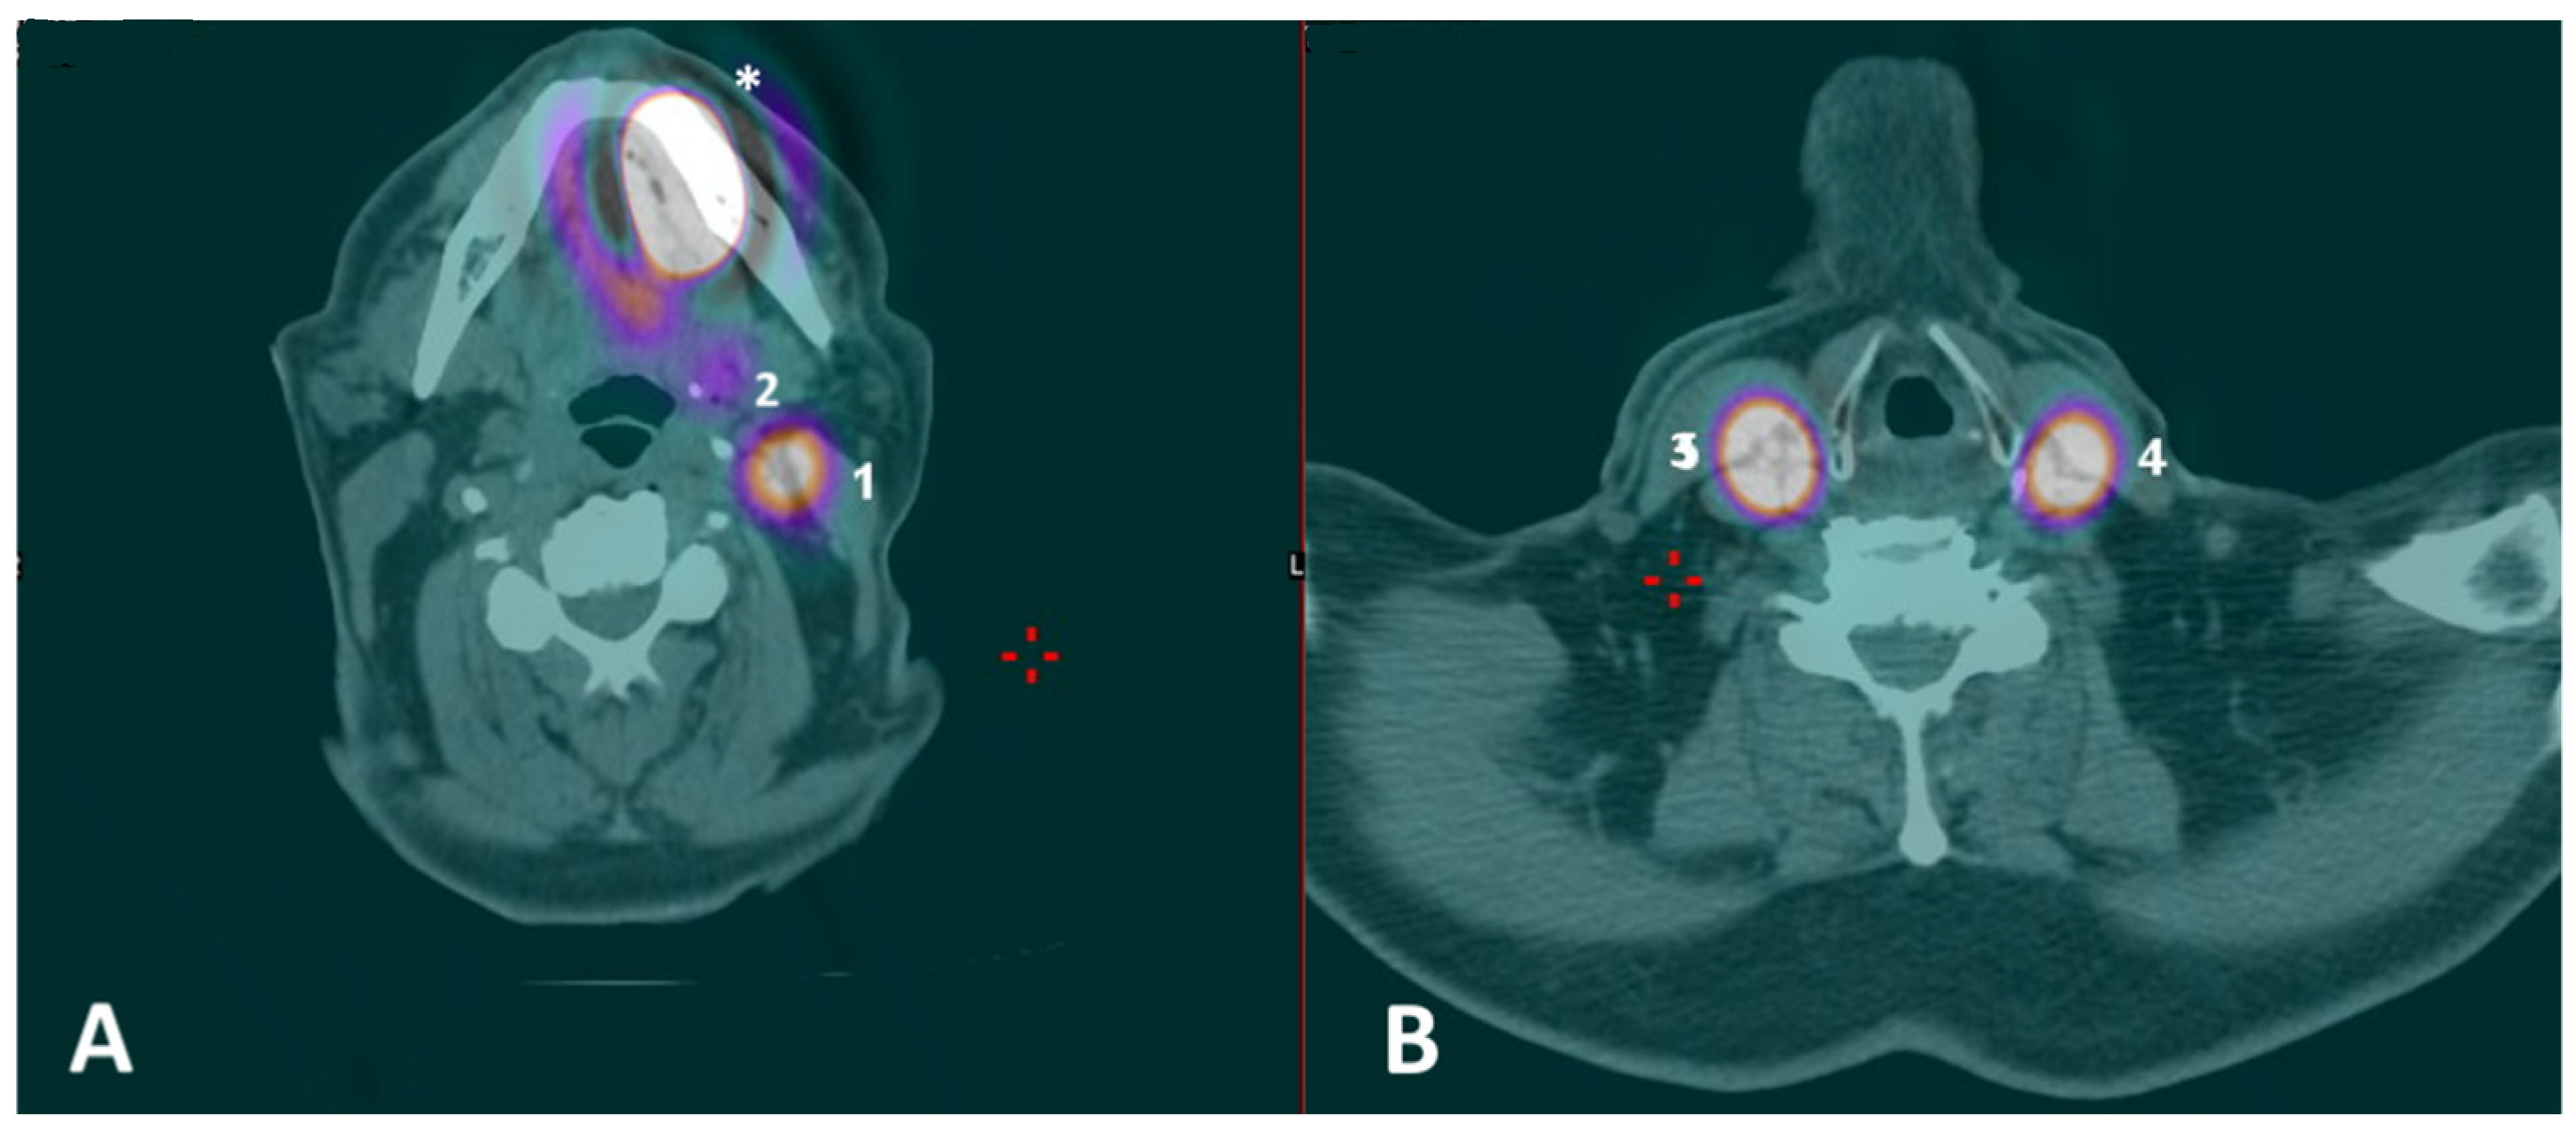

Figure 2.

(A,B) Preoperative SPECT/CT with identification of multiple nodal hotspots (lighter circular areas encircled by a purplish ring, or, for (2), the purplish region) at levels IB (2), IIA (1) and III (4) on the left side and at level III (3) on the right side; hotspot at the primary injection site was also visible (asterisk).

The combination of 99mTc-Tilmanocept with ICG in a single, hybrid tracer is not yet approved for clinical use by the FDA/EMA. Therefore, the proposed ICG fluorescence-guided SLNB protocol with 99mTc-Tilmanocept used as a radiotracer seems a viable “surrogate”, which is designed to overcome these specific issues. In particular, a multimodal, stepwise approach is advised: after 99mTc-Tilmanocept injection, preoperative SPECT/CT can identify the specific nodal hotspot(s) and, thus, define the surgical “roadmap”; subsequently, a portable gamma probe is used to intraoperatively pinpoint the SLN location within each nodal hotspot, with high specificity but limited spatial resolution. Finally, a NIRF system takes advantage of the fluorescence emitted by the ICG to provide intraoperative, high-definition optical guidance within each nodal hotspot with higher spatial resolution, allowing the safe identification of a “hot” and “fluorescent” SLN (i.e., double control). Effective optical guidance may indeed strengthen the radioguidance, increasing the sensitivity of the whole procedure, especially in terms of spatial resolution [11]. This is of paramount importance in the so-called “shine-through areas”, in which a substantial reduction in the unnecessary dissection of para-SLN nodes can be achieved. This latter consequence may further reduce morbidity, mostly in the submandibular region, and aid pathologists in step-serial analysis by limiting the specimens provided. As stated above, although hybrid tracers do exist (i.e., ICG-99mTc-nanocolloid) and have been validated for this purpose [11], they still do not include Tilmanocept for radioguidance, which would be ideal for such a complex anatomical site as the anterior oral cavity. Indeed, the ability of Tilmanocept to identify hotspots, even at level IB, near the injection site, was also demonstrated in our small series (Figure 2), and in experienced hands, could help to avoid the systematic resort to the superselective dissection of “preglandular fat pad”, preserving the theoretical advantages of SLNB. Thus, the proposed multimodal protocol may mimic the use of a single, hybrid tracer with simultaneous optical and radioactive receptorial guidance.